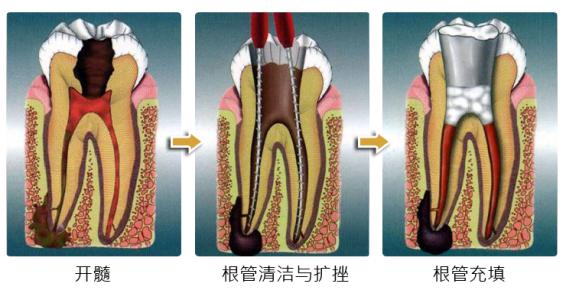

A:牙髓炎治療多半是選擇根管治療術,根管治療術在每個醫療機構,各級不同的醫療機構,醫生的水平的高低,以及所用材料的不同,還有牙齒牙位的不同等多種因素限制,所以治療費用不是一樣的。一般來說,在三級醫療機構根管治療的費用,如果單根牙大約在800-……

A:牙髓炎指牙面上有齲洞,齲洞引起了牙神經的發炎,牙髓炎發生以後可以進行根管治療術,根管治療術需要複診四次左右,費用根據牙位以及根管條件不同而不同。如果前牙單根管根管通暢,根管治療的費用是400元左右。後牙是多根牙,根管有3-4個,治療的費用……